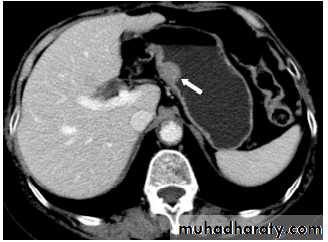

CT : IV contrast is usually given to emphasize the density between normal parenchyma and pathological lesions. The liver has dual blood supply from hepatic artery and portal vein. The liver is divided into 8 segments determined by hepatic and portal veins. The normal liver is higher or equal in density to the spleen. The normal intrahepatic bile ducts are not visible.

CT is more sensitive and specific. Lacerations and hematomas are recognized as low density areas relative to the normal intact, enhanced parenchyma. Leakage of contrast indicate active bleeding

At CT, liver density is less than splenic density